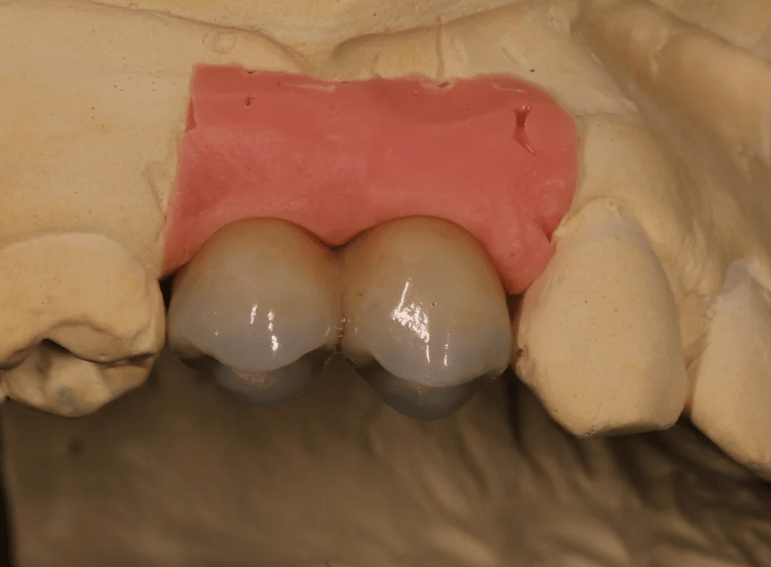

Replacement of retained primary teeth in a patient with hypodontia.